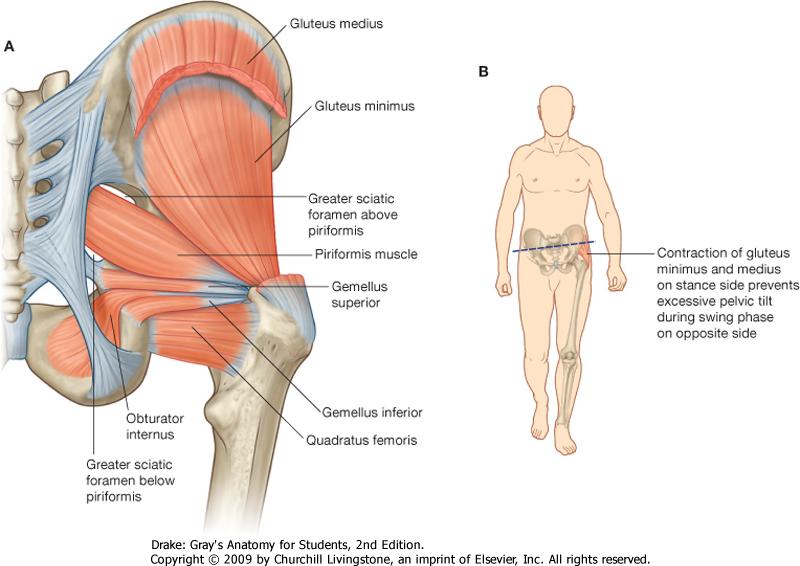

Анатомия мышц: Пириформис